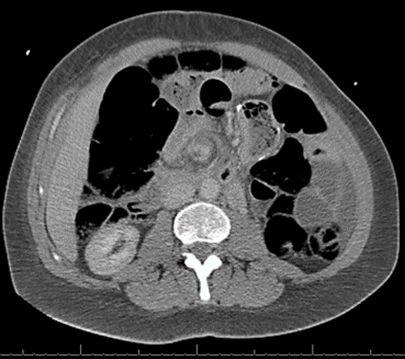

Een vrouw van 35 jaar meldt zich met hevige buikpijn op de SEH. Zij onderging eerder een cholecystectomie, een gastric bypass en een buikwandcorrectie. Een specifiek kenmerk op de CT-scan leidt naar de diagnose.